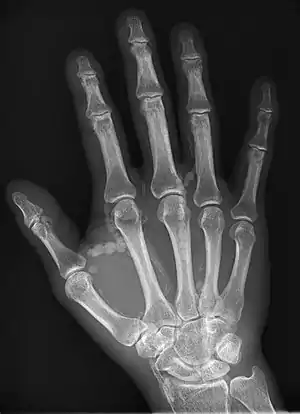

Oblique radiograph of the right hand demonstrating soft tissue calcification, characteristic of dialysis related metastatic calcification.